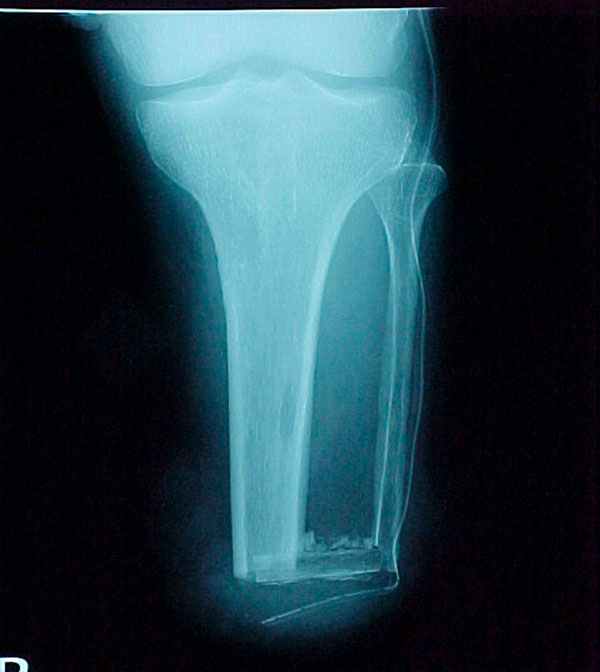

- Focus Area Reconstructive Surgery & Non-Surgical Management to Improve Bone Healing

- Sponsor DoD OETRP

- Primary Objective RCT to evaluate the use of recombinant protein in patients at high risk for nonunion